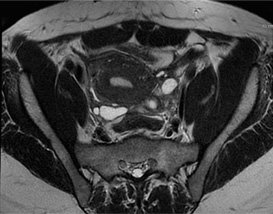

La lame d’épanchement intra articulaire du genou est une affection fréquente qui suscite de nombreuses interrogations. Cette accumulation de liquide